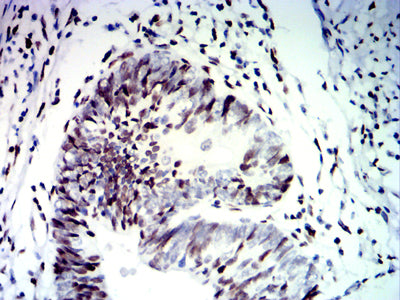

Immunohistochemical analysis of paraffin-embedded human bladder Cancer tissues using CDX2 mouse mAb with DAB staining.

Immunohistochemical analysis of paraffin-embedded human rectal cancer tissues using CDX2 mouse mAb with DAB staining.